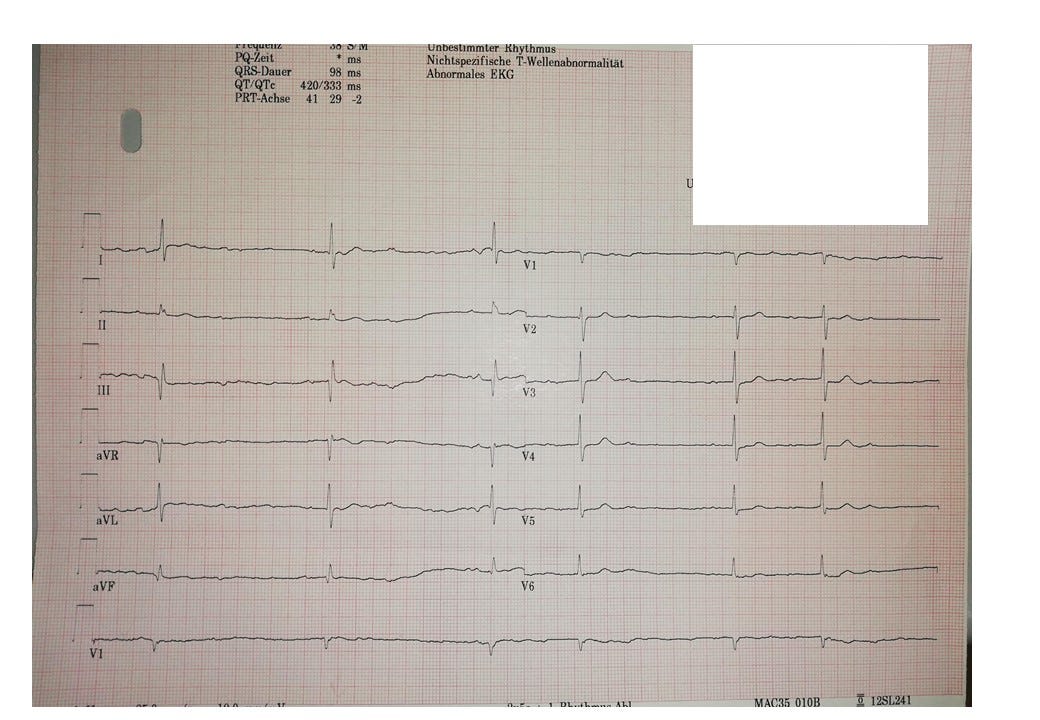

12-Kanal-EKG Befund